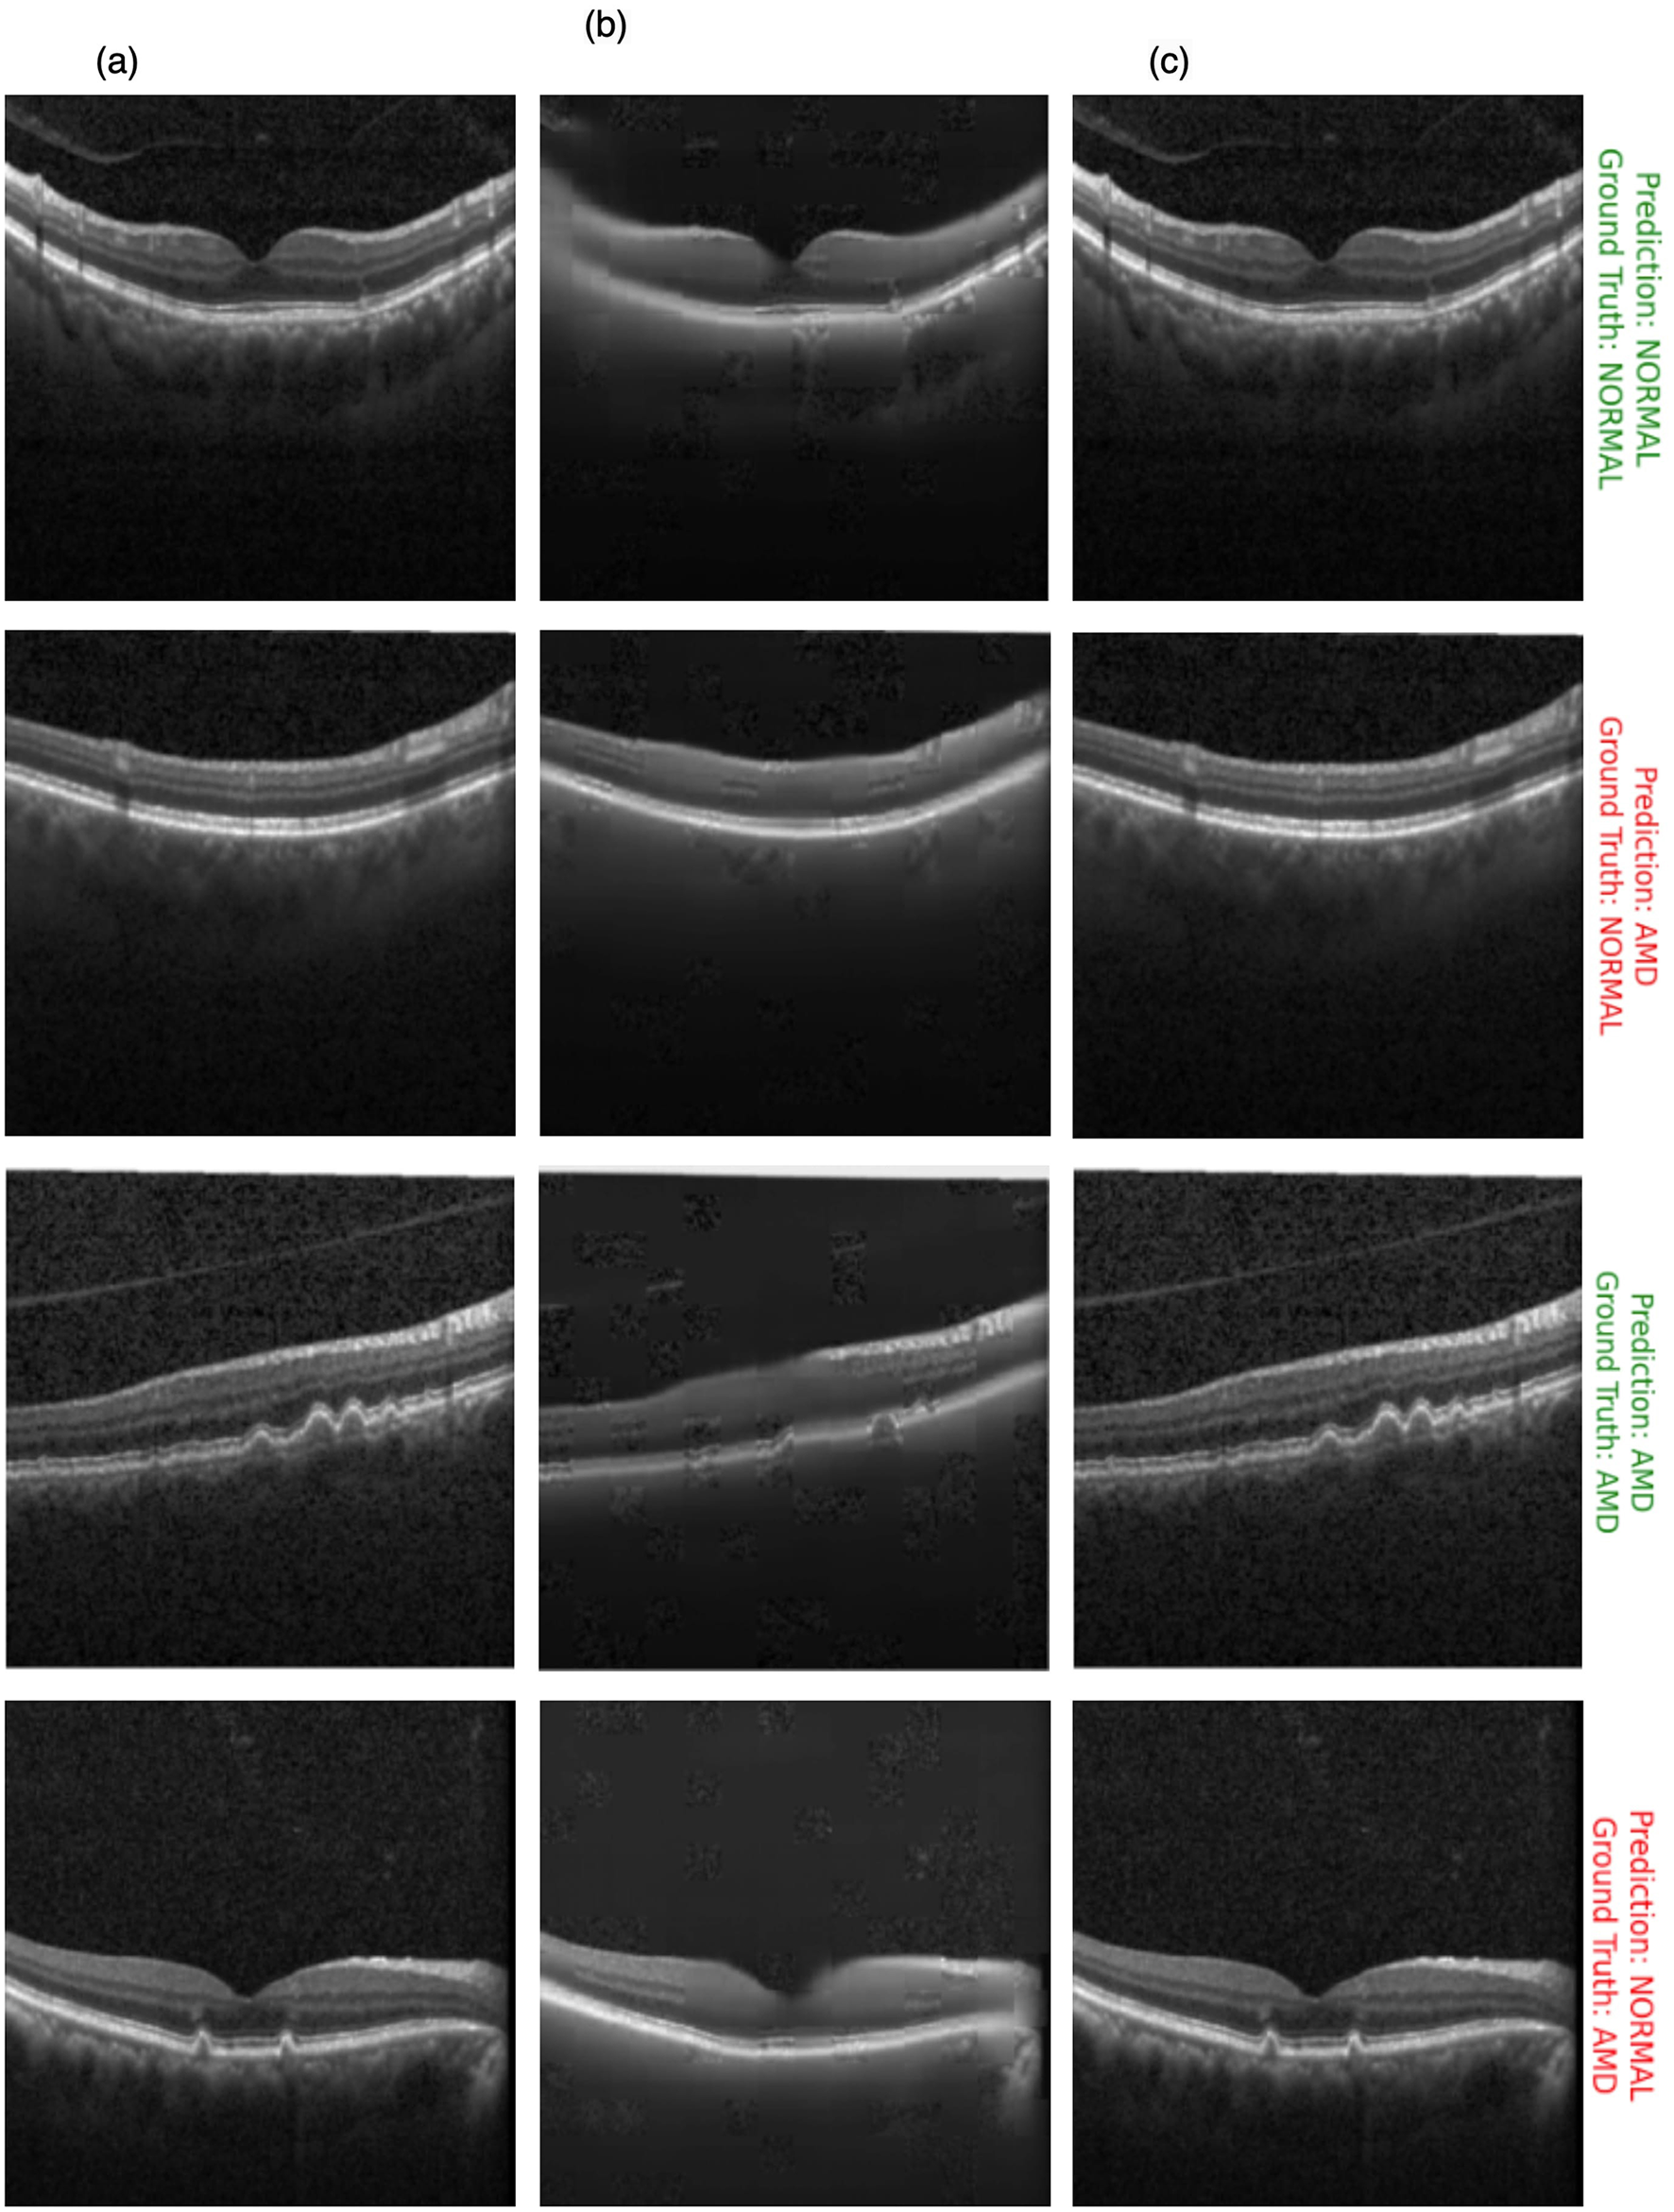

Figure 10 showcases the results of OCT image classification using the OCT-SelfNet-SwinV2 model. The figure displays a series of OCT images, each annotated with the model's prediction and the corresponding ground truth label. Correct predictions are highlighted in green, and incorrect predictions are marked in red. This visual representation facilitates an intuitive assessment of the model's performance in classifying OCT images across various scenarios, including true positives, true negatives, false positives, and false negatives. For each of these cases, two sample images are provided to illustrate instances where the model succeeded and struggled to make accurate predictions. This analysis reveals that the model encounters difficulties, particularly with visually challenging images to differentiate. In such cases, where the distinctions between categories like AMD and Normal are subtle or ambiguous, the model's predictions are less accurate. This suggests that the model's performance declines when faced with images that require more detailed visual interpretation, highlighting areas where further refinement may be needed.

Figure 10

OCT image classification results: this figure displays a series of OCT images with OCT-SelfNet-SwinV2 model predictions and ground truth labels. Each image is annotated with two lines: the first line shows the model's prediction (either AMD or Normal), and the second line indicates the ground truth category. Predictions that match the ground truth are highlighted in green, while incorrect predictions are marked in red.